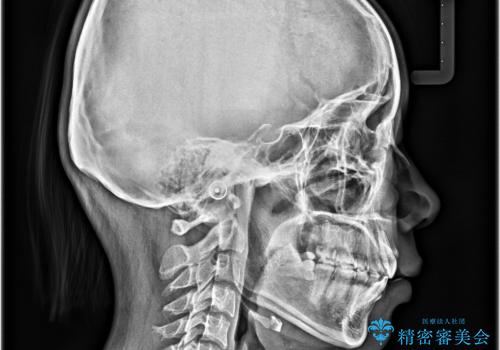

口元の突出感を治したい ワイヤー装置を用いた抜歯矯正

- 出っ歯と口の閉じにくさ、デコボコを気にして来院された患者様です。

口元の突出感を改善するため、上下左右第一小臼歯4本の抜歯を行い、ワイヤー装置による矯正治療を行うこととしました。

抜歯矯正を行ったことで、顎先のつっぱり感や口元の閉じにくさを解消することができました。